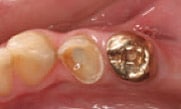

Figure 3

Roll Protemp™ Crown Temporization Material between gloved fingers

to soften.